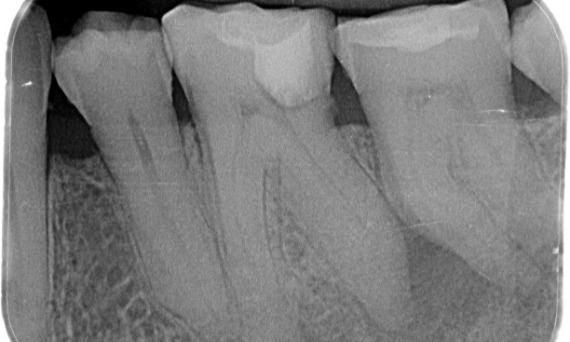

Antes: Radiolucencia periapical asociada principalmente con la raíz distal y pérdida de la lámina dura en la raíz mesial.

Después: En este caso, se eligió TruNatomy para permitir un enfoque apalancado en las caries y un enfoque en la conservación de la dentina pericervical, especialmente en el aspecto mesial donde el diente tuvo una restauración más mínima.

Dr. Jonathan Cowie (especialista en endodoncia)

Bath, Reino Unido